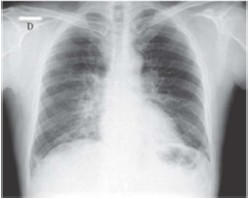

Paciente do sexo masculino, de 58 anos, empresário, natural e procedente de Goiânia – Goiás, procurou unidade de pronto atendimento relatando que há uma semana iniciou quadro gripal caracterizado por febre aferida (38,5 ºC), dores no corpo, coriza e obstrução nasal. Três dias depois, passou a sentir muito cansaço e mal-estar. Nesta ocasião procurou atendimento em unidade primária, onde realizou radiografia de tórax e recebeu o diagnóstico de pneumonia. Foi medicado com amoxacilina clavulanato por via oral, com a recomendação de retornar caso piorasse. Continuou cada vez mais cansado, retornando ao serviço de emergência novamente dois dias depois. Antecedente de hipertensão arterial em uso de losartana 50mg duas vezes ao dia. Nega outras comorbidades. Nega tabagismo. Ao exame físico, mostrava-se em regular estado geral, corado, hidratado, anictérico, cianótico +/4, dispneico +++/4, sem linfonodomegalias. Temperatura axilar de 36,8 ºC. Glasgow 15. Aparelho cardiovascular: bulhas rítmicas normofonéticas sem sopros, frequência cardíaca 110 bpm, pressão arterial de 130x90 mmHg. Aparelho respiratório: frequência respiratória de 32 incursões por minuto, com uso de musculatura acessória, ausculta pulmonar com estertores crepitantes difusos em ambos os pulmões. SpO2: 85% em ar ambiente. Abdome: nada digno de nota, sem visceromegalias. Extremidades sem edema. Peso 78 kg; altura 1,65m. Foi realizada uma nova radiografia de tórax (imagem abaixo) e coletados exames laboratoriais, incluindo hemoculturas e perfil virológico. Gasometria arterial colhida na entrada evidenciou: pH = 7,53; PaCO2 = 30 mmHg; PaO2 = 50 mmHg; bicarbonato = 24 mEq/L; base excess = +0,5 mEq/L; e SaO2 = 85%.

Considerando o caso clínico, o quadro sugere como diagnóstico